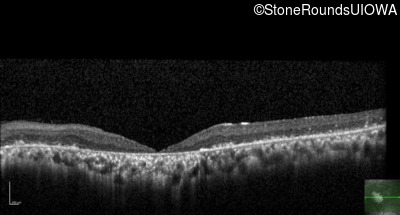

The clinical features supporting the diagnosis of Bardet Biedl syndrome in this patient include: bone-spicule-like pigmentation, narrowed arterioles and macular atrophy on ophthalmoscopy; photoreceptor loss on OCT; ulnar polydactyly, obesity, abnormal cognition, hypertension; and, normally sighted parents.